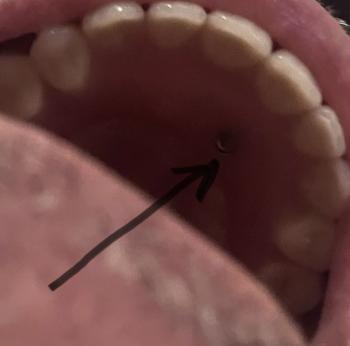

The image shows localized swelling and redness on the gum near the upper front teeth, visible when the patient pulls the lip back. The teeth appear generally intact, but the gum tissue around one or more front teeth looks inflamed and raised, suggesting a localized gum abscess or infection.

This area is part of the smile zone, so changes are easily noticed by the patient.